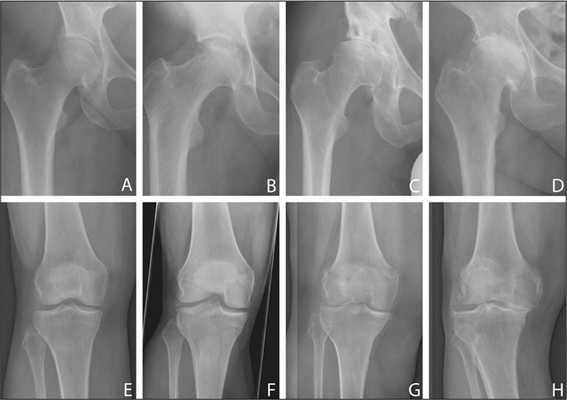

Динамика болезни на рентгене.

Откладывать хирургию при гонартрозах 3-4 степени чревато деформацией позвоночника. Это происходит из-за хромоты. Дегенеративные процессы артроза глубоко затронут кости, из-за чего они приобретут хрупкость, потеряют плотность и зафиксировать к ним компоненты импланта станет сложно.

Типы протезов и связанные с ними методики

Вы уже знаете, что бывает полное и частичное эндопротезирование коленного сустава, где в первом случае лечение подразумевает полноценную замену суставных поверхностей, а во втором - имплантацию поврежденного участка одного из мыщелков. Соответственно, протезы классифицируются на тотальные, одномыщелковые и ревизионные для замены импланта.

- После постановки однополюсной системы максимально сохраняется собственный костно-хрящевой сегмент и не затрагиваются связки, кстати, они должны быть в хорошем состоянии.

С каждой последующей операции статистика успешности ниже. Импланты при этом становятся все более громоздкими.

Одномыщелковое протезирование подразумевает срок службы небиологического устройства максимум 7 лет. Тотальное замещение предусматривает время службы вживленного механизма от 15 лет. Ревизионное переносится сложнее, а риск инфекции и других негативных явлений почти в 2 раза выше, чем после первичной операции.